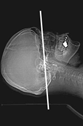

大腸CT(仮想大腸内視鏡)導入

内視鏡を使用せず、検査前に肛門から炭酸ガスを注入し大腸を膨らませた状態でCT撮影(仰向けとうつ伏せ)を行う新しい検査です。得られた画像にコンピューター処理を加え、仮想大腸内視鏡検査として診断を行います。大腸内視鏡検査に比べ比較的、前処置(検査前に大腸内をキレイにする)や検査中の苦痛が少なく、身体に優しい検査です。

大腸CT画像(正常部位) 大腸内視鏡画像(正常部位)

大腸CT画像(病変部位)  大腸内視鏡画像(病変部位)